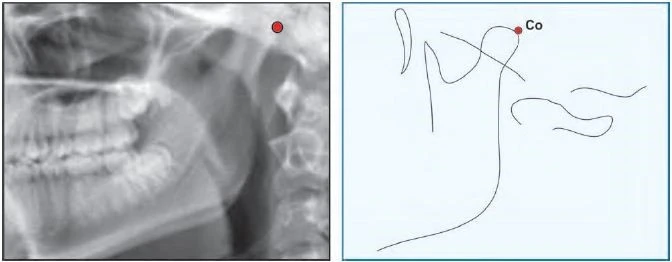

Condylion (Co) là điểm sau nhất và trên nhất ở lồi cầu xương hàm dưới.